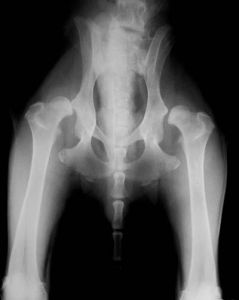

canineHipDysplasia簡稱CHD,中文稱作”髖關節發育不全症”,俗稱的說法是”大腿骨鎖不緊”,但不是”先天性脫臼”。CHD是出生後髖關節正常,但是由於骨頭生長太快肌肉生長速度跟不上,而使得股骨頭被肌肉牽引脫出脾臼關節而引起的,因為正常的髖關節發育情形是脾臼和股骨頭部(球體)之間,必須在整個成長期間都要能夠很緊密的彼此接合在一起,也就是說脾臼必須夠深,股骨頭的球體必須成形,並且讓股骨頭可以與脾臼窩緊密,深陷且完美地結合在一起。因為髖關節是承受體重的重要關節,主要是由球體與腔窩的結構所組成的。髖關節將骨盆與下肢連線起來,球體的部分是股骨(大腿骨)的端點,而腔窩(脾臼窩)則是骨盆的一部份。一個真正的球體與腔窩關連的關節,可以在三維方向上作自由活動,但狗狗的髖關節卻不是普通的球體與窩臼關係的關節,因為它可以有第四維方向上的自由運動:股骨的頭部(球體)可以往外離開脾臼。雖然是此關節最特殊之處(可以讓連線的附屬肢做任何方向的活動),但如果關節變得過於送弛,就可能會產生問題。因為當股骨的頭部向外側作太多的位移,而離開它原本在脾臼里的位置時,這樣就會讓髖關節在承受體重時產生較大的壓迫力及不正常的摩擦。因此,脾臼窩發育得不夠深而股骨頭的球體不夠成形並且接合送弛,股骨頭部的球體便非常容易離開脾臼里的正常位置,長期而日積月累下,髖關節在承受體重時持續產生較大的壓迫力及不正常摩擦,便會造成患犬的疼痛及關節的損傷與退化。嚴格來說,CHD是一種由許多共同疾病共同作用所導致髖關節的退化變質作用(DegenerativeEffects),這種疾病是由遺傳基因所產生的,但是由於涉及多基因性(牽涉多組不同的基因),共顯性的基因特質和多因素性(被許多非基因的因素影響)。因此是一種非常複雜的基因遺傳疾病,根據相關研究,就算是沒有CHD的狗狗,有可能產下患有CHD病症的狗狗,因為表面症狀沒有顯現CHD也可能有CHD的基因。相關的研究也顯示,後天的環境與飼養因素並不會產生CHD,也無法防止CHD發生,但是會加重或減緩CHD的症狀。如何判斷是否為CHD部分醫生都是以觸診或外觀來判斷,但是根據國外相關研究認為必須照射X光片由專業醫生診斷,才能正確無誤地判定是否為CHD,在美國有一個組織叫做OFA(OrthopedicFoundationforAnimals,網址:http://www.offa.org),只要繳納$10費用,就可以將X光片交給他們來判定,依據OFA的做法是兩歲以前只作評估,滿兩歲才做正式判定,因為兩歲以前狗狗還在發育有可能幼時由於股骨頭與脾臼的發育速度不一,產生髖關節發育不全的現象,然而也有幼犬時期髖關節發育是正常的,但是在成長過程,髖關節進行嚴重的結構改變,CHD才逐漸顯現,因此必須在發育完成後做最後判定。由於CHD是發展性的疾病,兩歲時如果沒有見到髖關節發育不全的症狀,才能判斷為無CHD,才可以作為繁殖用,在國外,患有CHD的犬是禁止繁殖的,除了同胎仔犬禁止繁殖,也會追溯至父母犬乃至上幾代相關的直系旁系犬一併停止繁殖,但是無CHD的狗如有75%的兄弟姊妹有CHD也不建議作繁殖用,該組織也將經該組織以判定合格的犬建立資料庫以供查詢。